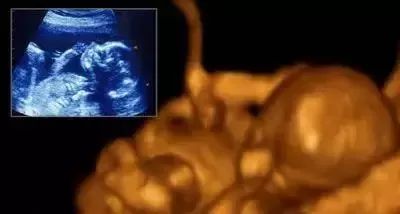

七个月:长度35-38厘米,体重1000克,脸像人一样。尽管如此,因为皱纹很多,看起来像个老人。如果子宫外面有一个长长的明亮的光,他会把头转向光束。他的脂肪组织继续积聚,为出生后母亲子宫外的生命做准备。

八个月:胎儿长到约43厘米长,重约1750克。它生长迅速,几乎充满整个子宫;他的指甲和脚趾甲已经完全发育;一些胎儿有长头发,有些只是轻微绒毛;你的宝宝在子宫中占据很大的位置。随着活动空间变小,胎儿活动减少,胎儿皮下脂肪逐渐生长,以适应子宫外的温度变化。